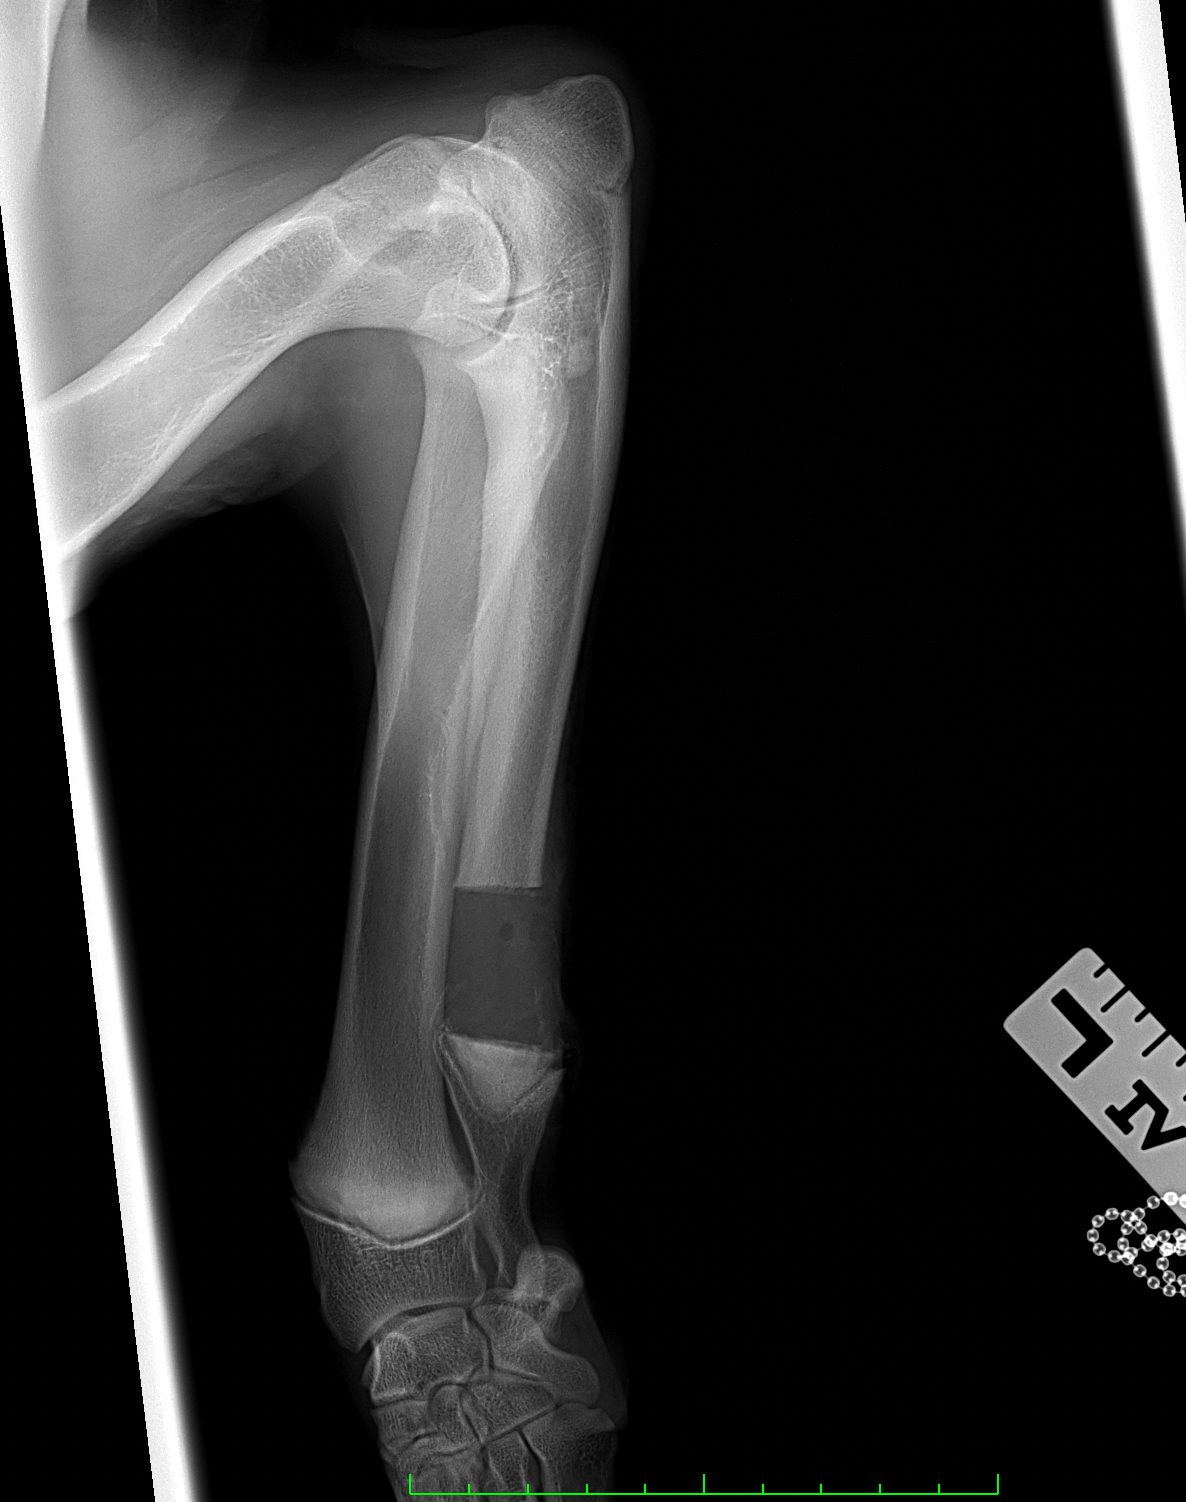

遠位尺骨部分切除術 大型犬のパピー(5mo)の前腕変形に対して、尺骨遠位骨部分切除術を実施。橈骨の成長が終了するまで待ってから変形による有痛症状があれば関節鏡による探査と橈骨の変形矯正を検討します。 症例カテゴリー 放射線治療整形外科軟部組織外科脳神経外科内科腫瘍外科救急・集中治療リハビリテーション科腫瘍内科内視鏡科脳神経科呼吸器外科中医・漢方猫の腎移植循環器科